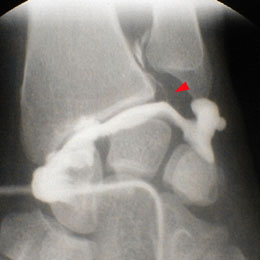

A - Arthrographie de la radiocarpienne : Début de remplissage de la radio-cubitale-inférieure par une fissure communicante du ligament triangulaire. A noter, une variance ulnaire nettement négative.

B - Arthrographie de la radiocarpienne : Nette opacification de la RCI.

Fissuration communicante (Classe 1A) du ligament triangulaire.